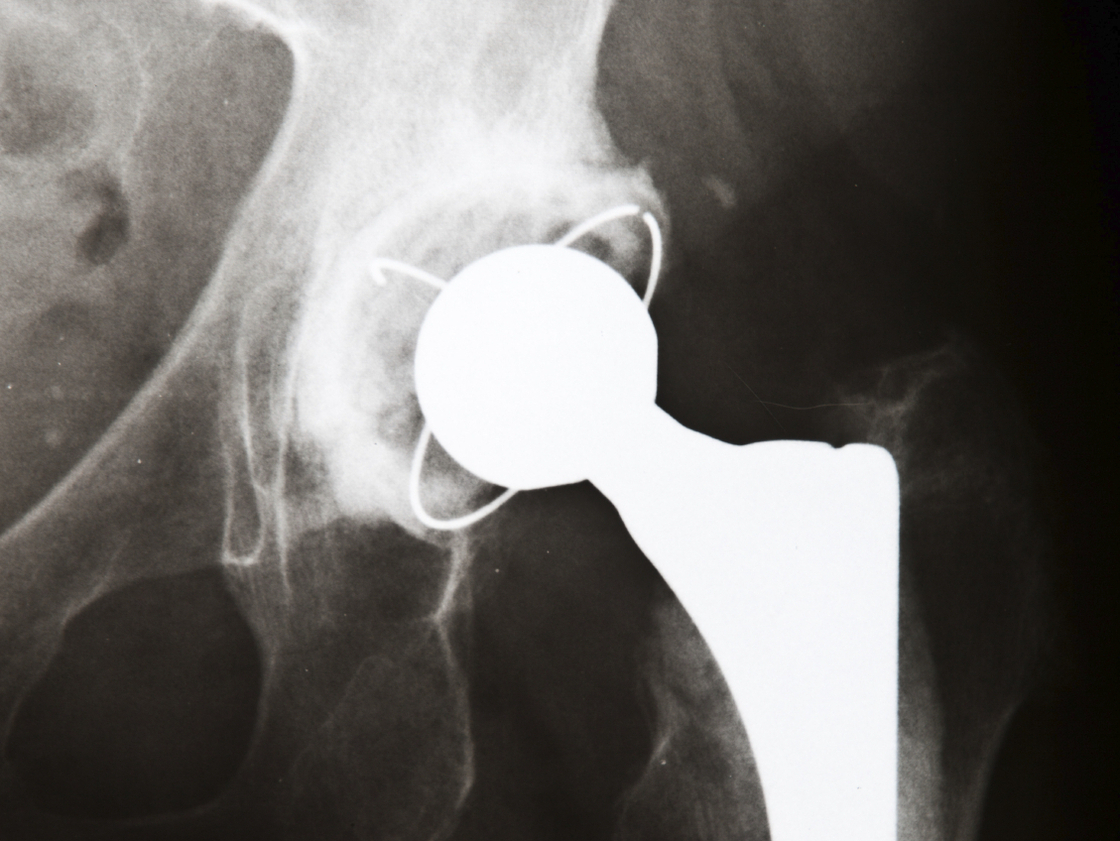

According to WebMD, the following tips make recovering from a joint replacement easier.

• Stair climbing should be kept to a minimum of no more than once a day.

• Avoid reclining chairs. A good stiff backed chair is always best.

• Pick up all throw rugs.

• Keep energetic pets away.

Post-operative care and having the correct medical equipment can aid in a healthy recovery from any surgery. Shop AllegroMedical.com for a large selection and low prices on daily living aids and other joint replacement medical supplies.